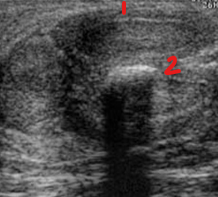

Identify this image.

Prostatic cancer

Thin tunica albuginea

Plaque formation seen with Peyronie disease